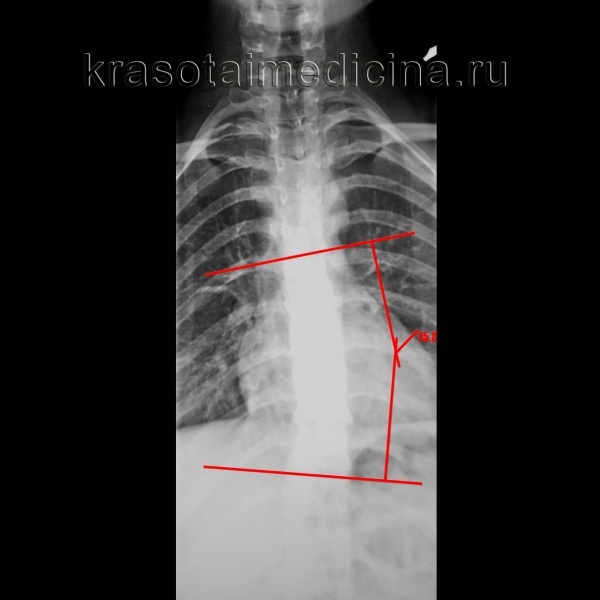

Рентген грудного отдела позвоночника. Левосторонний сколиоз 2 с углом дуги приблизительно 15,8 градусов (Кобб) с центром в Th9.